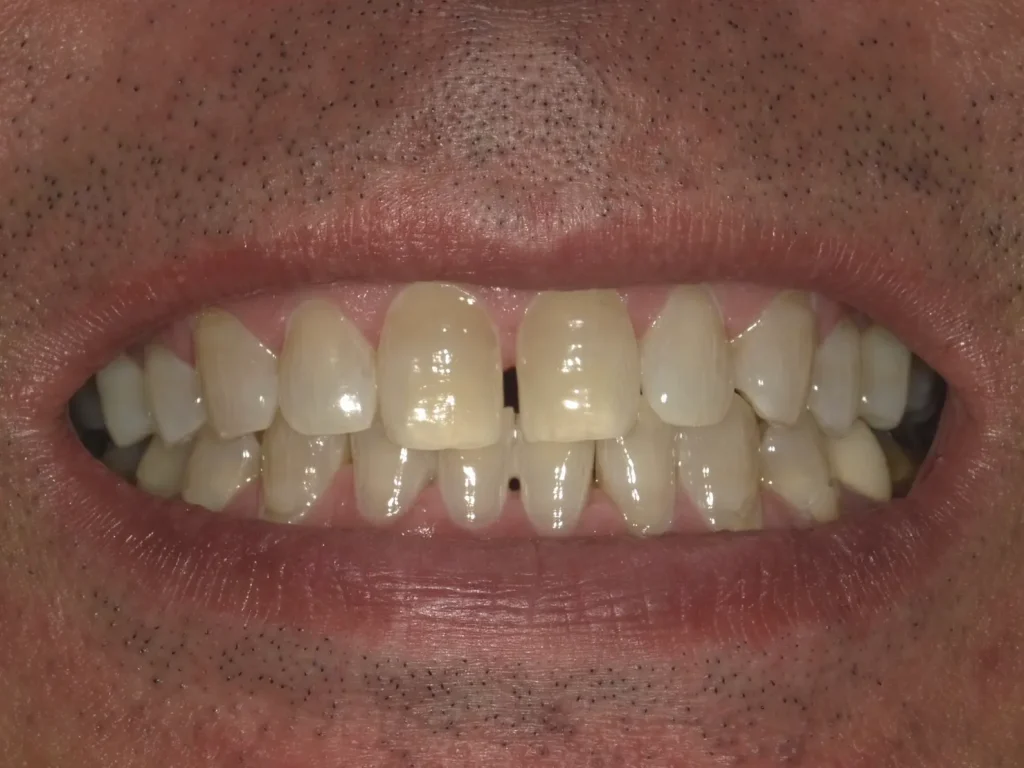

術前術後写真